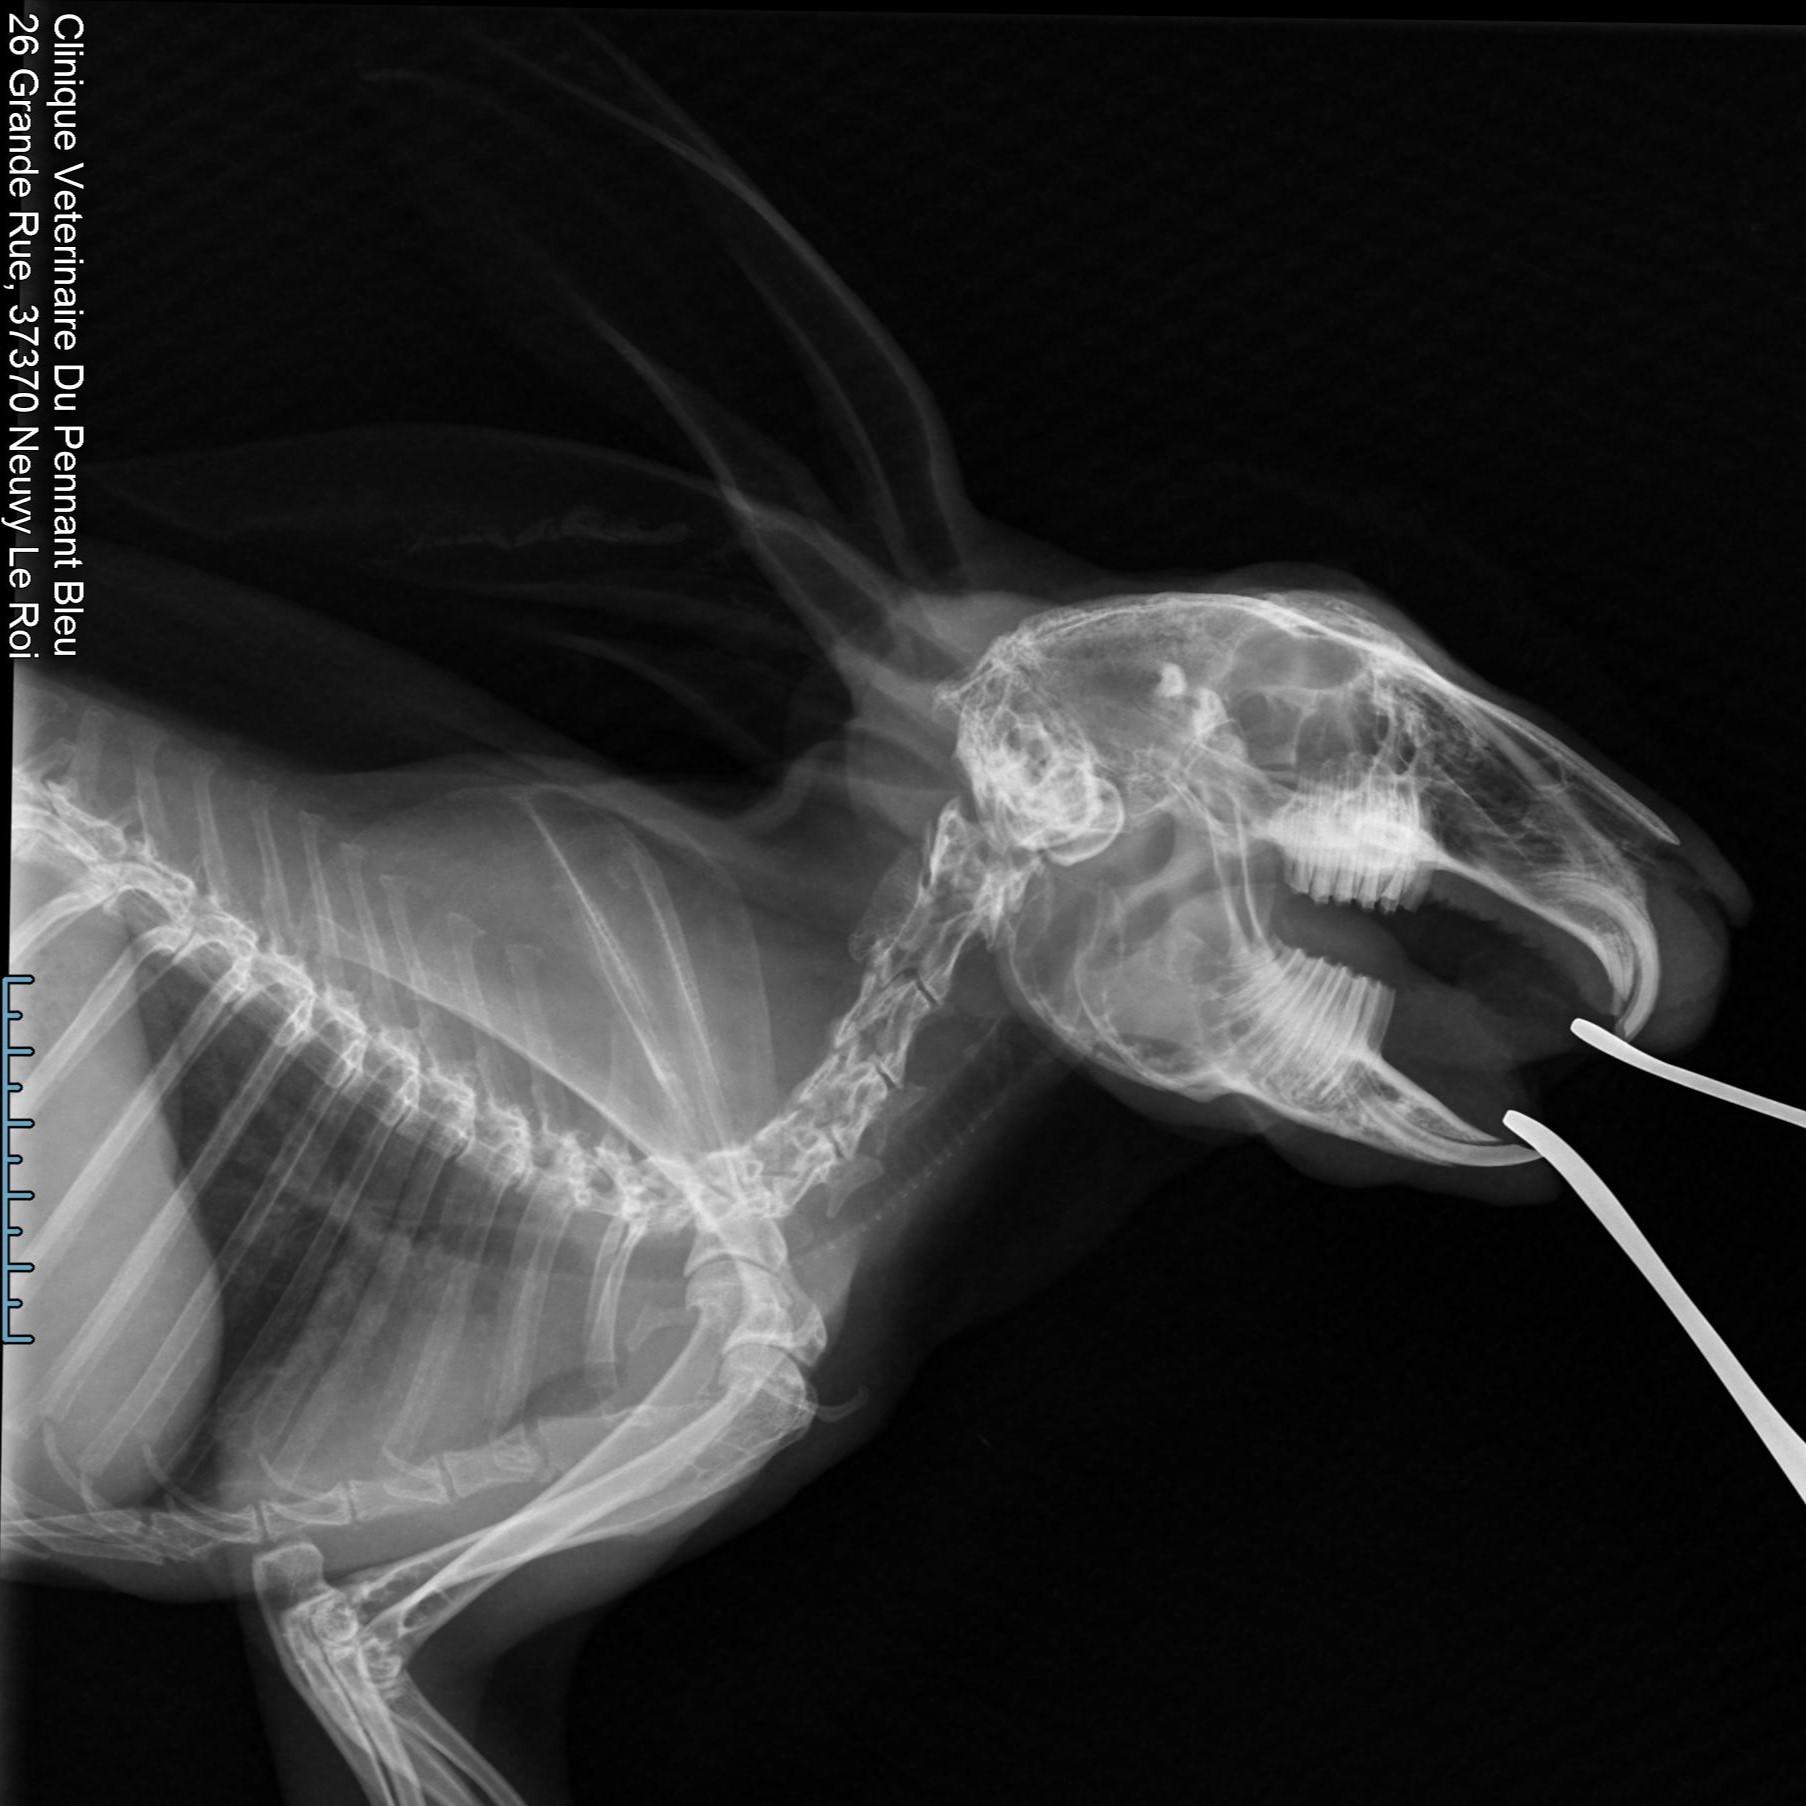

Imagerie

Les différentes technologies d'imagerie aident aux diagnostics : radiologie, échographie, endoscopie...